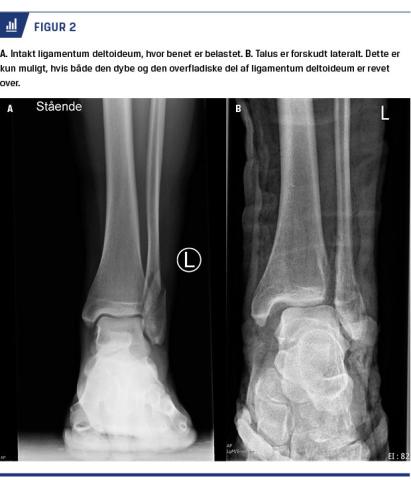

Stabiliteten af ankelleddet afgør, om en fraktur kan behandles konservativt eller ej. I tilfælde af isoleret lateral malleolfraktur afgør integriteten af ligamentum deltoideum, om ankelleddet er stabilt. Hvis den dybe del af ligamentum deltoideum er ødelagt, vil ankelleddet være ustabilt, idet talus kan forskydes lateralt. Er det derimod intakt, vil talus blive holdt på plads på trods af den frakturerede laterale malleol (Figur 2).

Weber et al påviste, at røntgenbilleder, der bliver

optaget, mens patienten belaster foden, er en let og pålidelig måde at afgøre stabiliteten af ankelleddet på [23]. Røntgenoptagelserne skal tages uden bandage

eller med aftagelig ortose, da gips vil forhindre belastning på foden. Det kan være hensigtsmæssigt at vente nogle dage med at tage disse optagelser af hensyn til smerter i ankelleddet ved belastning. Hvis røntgenbilleder af den belastede ankel ikke viser diastase mellem talus og den mediale malleol, er ligamentum deltoideum intakt, og den isolerede laterale malleolfraktur kan behandles konservativt. Andre test såsom gravity stress test og udadrotationstest kan også anvendes, men der er ifølge enkelte studier en tendens til at overvurdere instabiliteten ved disse test [24, 25].